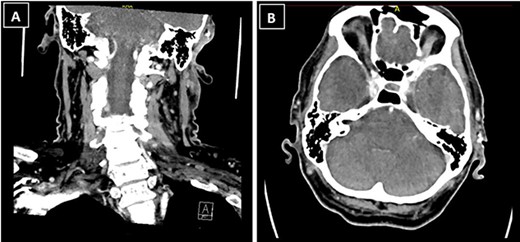

The patient’s case was discussed at the skin cancer multidisciplinary team meeting and he underwent imaging of the area for further evaluation, given the histological diagnosis. Computed tomography (CT) neck showed a 1.3 × 1.2 × 1.3-cm ill-defined soft tissue enhancement above the left external auditory canal involving the subcutaneous tissue and overlying skin (Fig. 3). There was involvement of the superior and superficial aspect of the parotid gland. CT thorax, abdomen and pelvis showed no evidence of distant metastases.

CT neck showed a 1.3 × 1.2 × 1.3-cm ill-defined soft tissue enhancement above the left external auditory canal involving the subcutaneous tissue and overlying skin; (A) coronal view; (B) axial view.

The patient underwent further wide local excision which revealed negative margins. Positron emission tomography CT after re-excision of margins showed no FDG avid areas, indicating no remaining disease. The patient went on to have adjuvant radiotherapy.